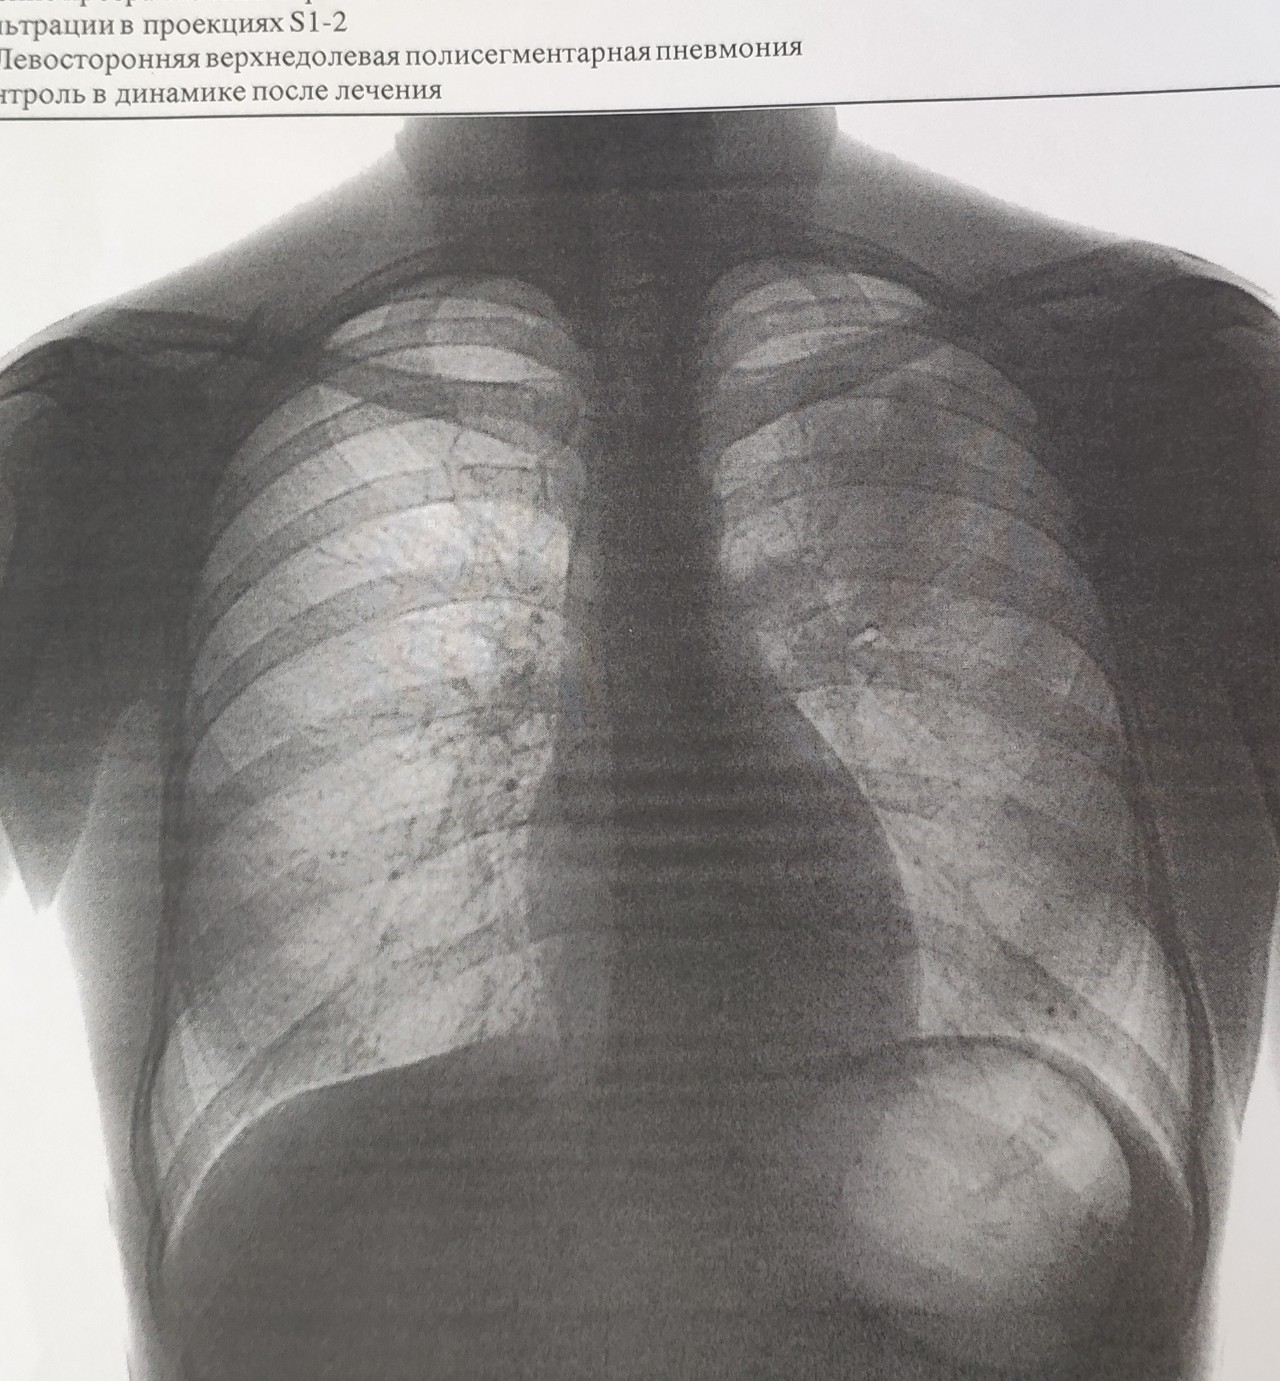

Рентген здоровых легких: примеры снимков и советы

Раздел: Сокровищница опыта